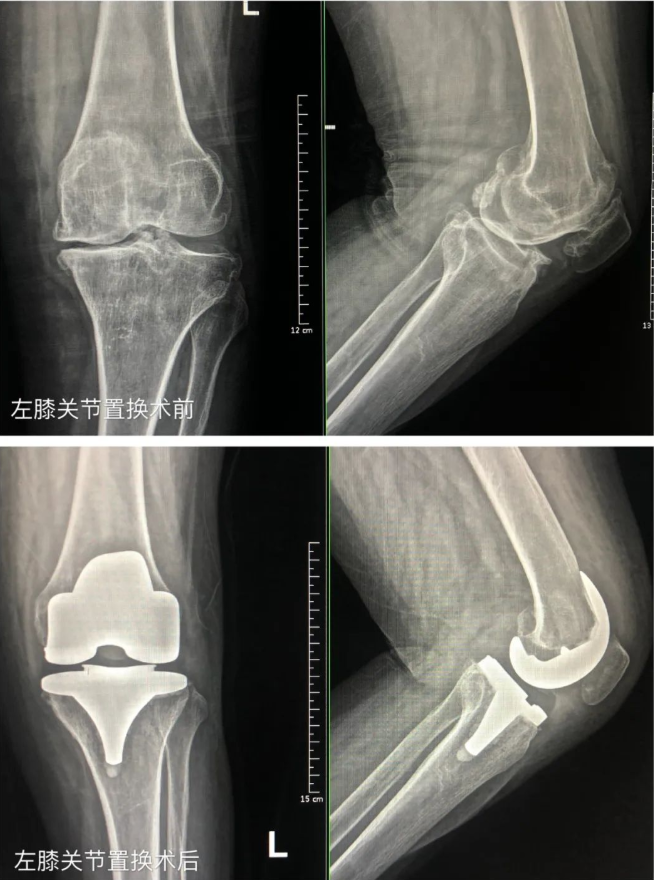

接着他们又来到了不远处的张大娘家。张大娘几年前就查出患有膝关节疾病,走路都得拄着拐杖,平时提个水、做个饭都需要别人帮助,严重的影响了生活。无奈张大娘老伴走的早,孩子虽已经成家但经济条件都一般,实在拿不出更多的钱来为老人治病。

2个月以前,中德骨科医院联合慈善总会来到沂水县做慈善义诊救助活动,张大娘正好符合条件,被接到医院进行免费进行了手术,还为她免去了其他治疗费用。“俺听说,给俺看好病的恩人要来,俺激动的一晚上都没睡着觉,俺一定要当面谢谢他们”。得知医院的专家要来,张大娘一大早就在村口等着。“俺现在能提水做饭、看孙子,还能下地干活,俺的日子又有了奔头了,这得感谢党和政府,感谢中德骨科医院的专家”,张大娘激动的说!

王院长将慰问品亲自交到老人的手中,并为她进行了详细的检查。经了解发现,张大娘恢复良好,已经回到了发病前的状态。同时,他叮嘱张大娘一定不能急着干重活,注意休息,有机会的话可以再次到医院进行免费复查。